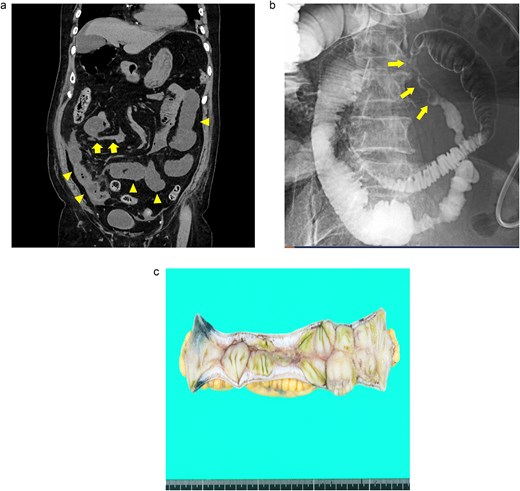

A 76-year-old man presented with a gradual onset of intermittent epigastric and left abdominal pain. Three months prior, he experienced similar pain, and computed tomography (CT) revealed hepatic portal venous gas (HPVG) without mesenteric ischemia or bowel strictures. The patient’s symptoms resolved with conservative treatment, none of the CT features during follow-up. His vital signs were stable, and laboratory test results were normal, including a white blood cell (WBC) count of 8800/μl, C-reactive protein (CRP) concentration of 0.02 mg/dl, hemoglobin (Hb) level of 12.5 g/dl, and lactate (Lac) concentration of 0.7 mmol/l. CT enterography revealed a segmental stricture with wall thickening in the distal ileum (Fig. 1a). Double-balloon endoscopy (DBE) revealed a circumferential ulcer and segmental stricture in the distal ileum. Fluoroscopy during DBE confirmed segmental, smooth luminal narrowing in the distal ileum (Fig. 1b).

Case 1: (a) CT enterography with water-soluble contrast agent. The arrowheads indicate a segmental stricture with wall thickening in the distal ileum. (b) Fluoroscopy during double-balloon endoscopy. The arrows indicate a segmental, smooth luminal narrowing in the distal ileum. (c) Macroscopic view of the resected specimen. Circumferential ulceration is visible in the affected area.

Exploratory laparoscopy revealed a 10-cm-long segmental bowel stricture with wall thickening 50 cm from the ileocecal valve, which was resected. The pathological specimen revealed a circumferential ulcer with granulation tissue at the stenotic site, accompanied by edematous mucosa and fibrotic submucosa in the surrounding areas. No signs of tumors or inflammatory bowel disease (IBD) were noted (Fig. 1c). The postoperative course was uneventful, and the patient was discharged on the ninth postoperative day. By the 10-month follow-up, he had not had any recurrences of abdominal symptoms.